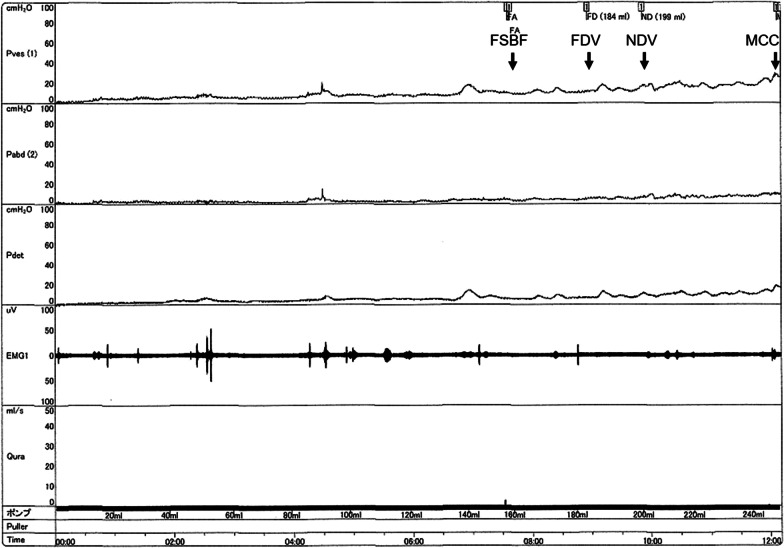

Fig. 4.

Urodynamic study during treatment with orally administered vibegron after changing from propiverine. FSBF first sensation of bladder filling, FDV first desire to void, NDV normal desire to void, MCC maximum cystometric capacity

A 4-year-old Filipino girl was referred to our hospital due to increased frequency of daytime urinary incontinence and foul-smelling urine since the age of 3. She was diagnosed with a lumbosacral myelomeningocele at 21 weeks of pregnancy and born to non-consanguineous parents at 37 weeks of gestation, weighing 2908 g. She underwent myelomeningocele repair 2 days after birth and did not have hydrocephalus. She was able to walk unaided 11 months after birth. Although she had a history of recurrent UTIs, she did not visit a urologist office regularly after surgery. At her first visit to our hospital, her physical and neurological examination was normal, that is, she had a maximum Glasgow Coma Scale score, steady gait, and no paralysis in her legs, and could run as much as other healthy children of the same age. She had a normal bilateral reflex knee jerk and Achilles tendon reflex. Clinical examination revealed constipation and no flexion contractures of her legs. Urinalysis revealed bacteriuria. Magnetic resonance imaging (MRI) revealed a tethered spinal cord (TSC) and syrinx at the S2–3 levels (Fig. 1). A pediatric voiding cystourethrography revealed an enlarged and trabeculated bladder without any vesicoureteral reflux. A urodynamic study (UDS) showed detrusor overactivity and low bladder compliance (1.8 mL/cmH2O). The maximum cystometric bladder capacity was 67 mL, with no specific bladder sensation, and the detrusor leak-point pressure was 77 cmH2O. She was unable to void. She was diagnosed with overflow incontinence (Fig. 2). Clean intermittent catheterization (CIC) was performed and 10 mg of propiverine (0.8 mg/kg body weight/day) was administered orally, and her urinary incontinence resolved. She underwent repeated UDS annually. A UDS at 6 years of age (she had been receiving propiverine for 2 years and 5 months) showed detrusor overactivity and low bladder compliance (3.7 mL/cmH2O), in spite of receiving 10 mg of orally administered propiverine per day. The maximum cystometric bladder capacity was 101 mL, and detrusor leak-point pressure was 50 cmH2O (Fig. 3). She had no urinary incontinence or UTI. However, the cystometrogram showed that her bladder pressure was persistently high. To reduce pressure on the urinary bladder, and avoid the risk of upper urinary tract damage, treatment was switched from propiverine to vibegron, a beta-3 adrenoceptor agonist. After obtaining the patient’s and parental informed consent, a single daily dose of 25 mg of vibegron (Beova; Kissei Pharmaceutical Co., Ltd., Tokyo, Japan) (1.4 mg/kg/day) was administered. After 5 weeks of once-daily vibegron treatment, UDS was performed and showed disappearance of detrusor overactivity, increased maximum cystometric bladder capacity (251 mL), and improved bladder compliance (9.0 mL/cmH2O) (Fig. 4). She has continued to receive vibegron that has been well tolerated and to perform CIC for 7 months so far, and no UTI, incontinence, or drug-related adverse events have been observed. No abnormalities were found in blood pressure (98/60 mmHg) or heart rate (72 beats/min) or on the blood tests after a month of receiving vibegron. Her detailed laboratory data (before and after taking vibegron) are presented in Table 1.